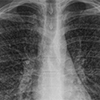

Case report describes new type of vaping lung injury

A team of authors including Schulich Medicine & Dentistry faculty members have released details on Canada’s first published case of suspected vaping-related lung injury. Published today in CMAJ, the case study may be the first to describe a new type of injury from vaping products.